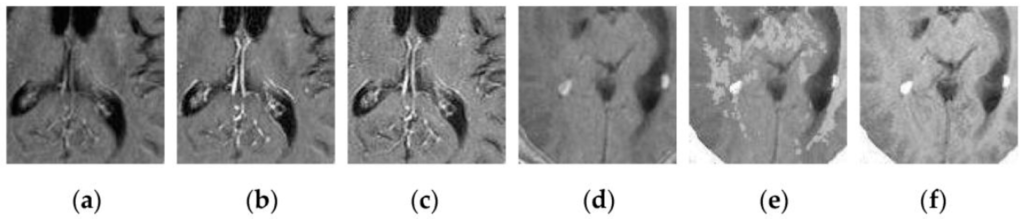

4.2. Visual Comparisons of Fused Results